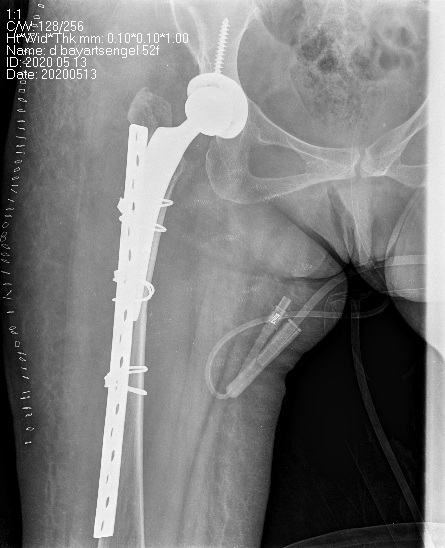

Periprosthetic fracture-Хиймэл үе суулгасны дараах хугарал

Хугарал засах мэс засал image10Хугарал засах мэс засал image11

Өвчтөн Б 52 настаЙ эмэгтэй 2020 оны 04 сард дунд чөмөгний хүзүүний эмгэг хугаралын улмаас түнхний үеийг бүтэн солих мэс засал хийлгэсэн. Мэс заслын дараах 25 дах хоног дээр явганаас халтирч унаж дахин хугаралыг зассан үеийн рентген зураг